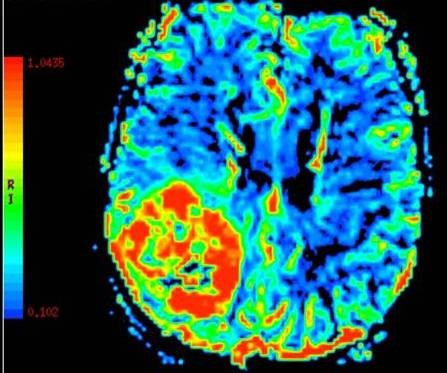

Dynamic Susceptibility Contrast MRI Perfusion image A for Radiology

How it works: Dynamic Susceptibility Contrast or DSC is a method of measuring cerebral blood flow, or blood flow to the brain. The technique requires intravenous contrast delivered through an automated power injector attached to an IV. The scanner creates an image showing multiple cerebral perfusion parameters including cerebral blood flow, mean time to enhance, and negative enhancement integral or cerebral blood volume. These techniques are most beneficial to patients with vascular stenosis, stroke, and brain tumors.

Equipment: Our MRI suite uses the latest Phillips 3.0 tesla magnets coupled with a state of the art Phillips Clinical Cerebral perfusion software package. Processing is performed by the technologist as soon as the scan is completed and images are available for immediate interpretation.

Dynamic Susceptibility Contrast MRI Perfusion image B for Radiology

Benefits: DSC perfusion gives the most thorough evaluation of cerebral blood flow. In addition to flow, the technique gives other parameters such as blood volume and transit time that allow the neuroradiologist to more accurately depict the true state of the brain perfusion. These additional parameters have been thoroughly studied with regard to stroke and tumor evaluation.1

Stroke and TIA: The perfusion parameters can show brain tissue at risk of stroke before the stroke has occurred. The best example of this is a patient with a transient ischemic attack or TIA . These patient's have brief stroke like symptoms and but may have a normal MRI. DSC perfusion can reveal subtle perfusion changes that could allow possible therapeutic interventions to prevent a future stroke.

Tumors: Cerebral blood volume correlates with the tumor grade or how malignant the tumor is. Brain tumors are frequently heterogeneous when looked at under the microscope. Perfusion can help guide the neurosurgeon to obtain the most accurate biopsy sample of the tumor to optimize therapy after surgery. Perfusion can also help distinguish a brain metastasis, primary brain tumors, and an infectious process prior to surgery.

Exam Preparation: The technologist will interview you prior to scan to make sure you have no contraindications to being in the MRI scanner. Patients with braces or other metal near the head or neck may not be suitable for DSC because of the artifacts the metal can cause. Patients who have kidney problems may not be able to get MRI contrast without being consented by a radiologist. If you think you have problems with your kidneys please let the technologist and scheduler know. Blood lab values may be obtained prior to the MRI scan to determine if you can receive MRI contrast safely. Patients will be given an IV prior to entering the MRI scanner.

What to expect: DSC perfusion alone takes approximately 2 minutes of scanner time. While the contrast is being injected, the scanner is dynamically acquiring images through the brain. It is very important to remain very still during this portion of the examination. The study is done in conjunction with routine anatomic imaging.

Content by Dr. Jeffrey Pollock